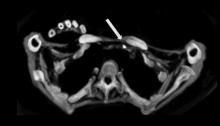

New research published in June issue of Global Heart (the journal of the World Heart Federation) show that there are no significant differences in the incidence or severity of atherosclerotic disease (narrowing of the arteries with fatty deposits) between ancient and modern people, showing that atherosclerosis is not just a disease of modern times. The journal included three articles [1,2,3] on the finding of the HORUS Study, which used CT scans from ancient mummies to compare arterial calcification caused by HORUS atherosclerosis.